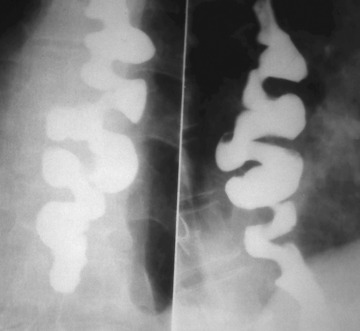

바륨현탁액, 요오드제제를 이용해 위의 이상 유무를 검사합니다. 이 용액은 X선 투과가 잘 안되는 물질로 이 용액을 마시고 X선이 발생되는 기계 위에서 몸을 이리저리 돌려가면서 검사를 받습니다. 기계가 알아서 돌아가는 것이 아니라 사람이 직접 그 기계 위해서 몸을 움직여 줘야 합니다.

X선이 발생하는 기계 위에 있으므로 그 방사선이 몸을 투과하므로 미량의 방사선 피폭이 있다는 것은 인지해야 합니다. 위조영술 검사방법은 위를 풍선처럼 팽창시켜 위벽에 조영제 코팅해 위벽 병변 유무를 검사하는 방법과 위가 팽창하지 않은 상태에서 위를 조영제로 채워 검사하는 두가지 방법이 있으며 일반적으로 두가지 다 시행해야 위벽과 안을 다 검사 할 수 있습니다.

하지만 위조영술 검사 장점도 분명히 존재합니다. 이는 그래도 위내시경 검사처럼 굵은 카메라를 삼켜야 하는 불편함이 없으며 노인이나 기저질환이 있는 환자도 위 검사를 받을 수 있고 식도에서 위 그리고 십이지장으로 이어지는 위장관의 전체적 모양과 연동운동을 관찰 할 수 있다는 점입니다.